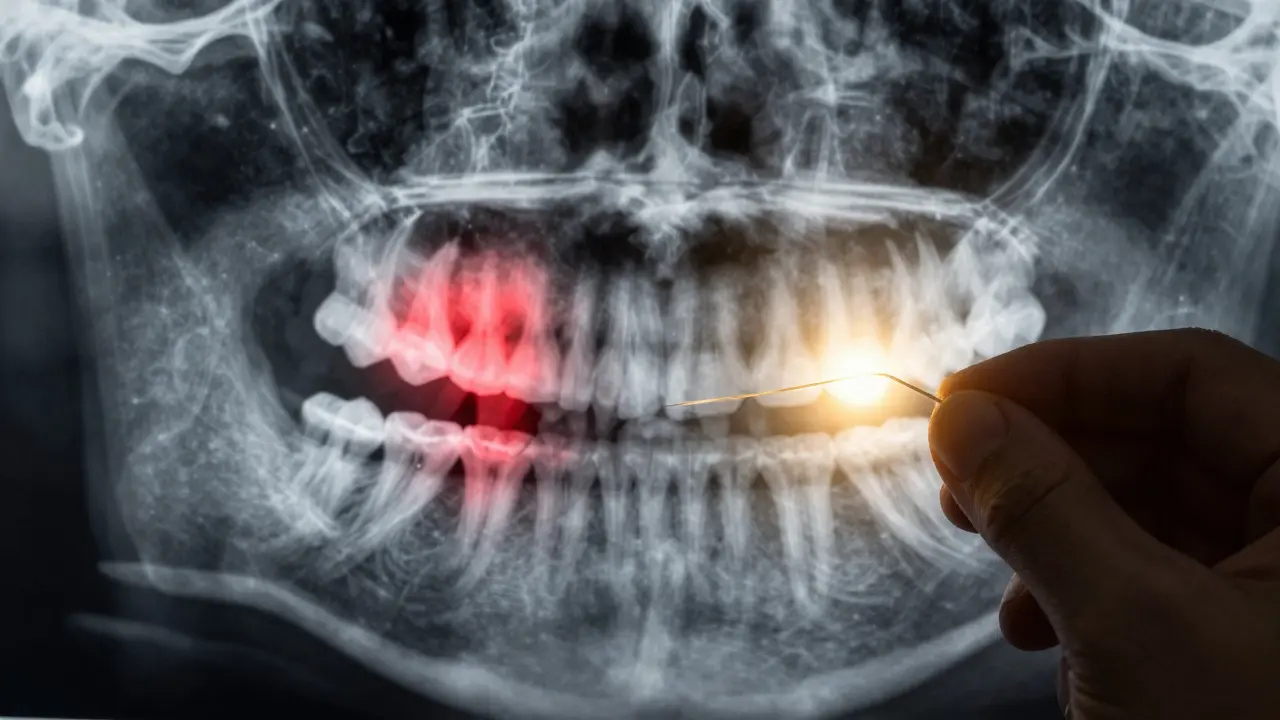

Zubní lékaři doporučují roční rentgen mezizubních oblastí - ne jen jako kontrolu, ale jako prevenci. Rentgen ukáže kaz, který ještě není vidět na povrchu. A pokud ho najdou včas, stačí jen zacelit malou díru - bez bolesti, bez kořenového léčení, bez ztráty zubu.

Rentgen ukazuje skrytý kaz mezi zuby, zatímco floss zabraňuje jeho šíření.